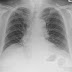

CASE 819: LEFT CHEST PAIN and LUNG POCUS, Dr PHAN THANH HẢI, Dr LÊ THỊ THANH THẢO, MEDIC MEDICAL CENTER, HCMC, VIETNAM.

A 67 year-old man with left chest pain progressing for 3 days, coughing and no fever. Lab data nothing abnormal detected.  EKG  sinus arrhyt...